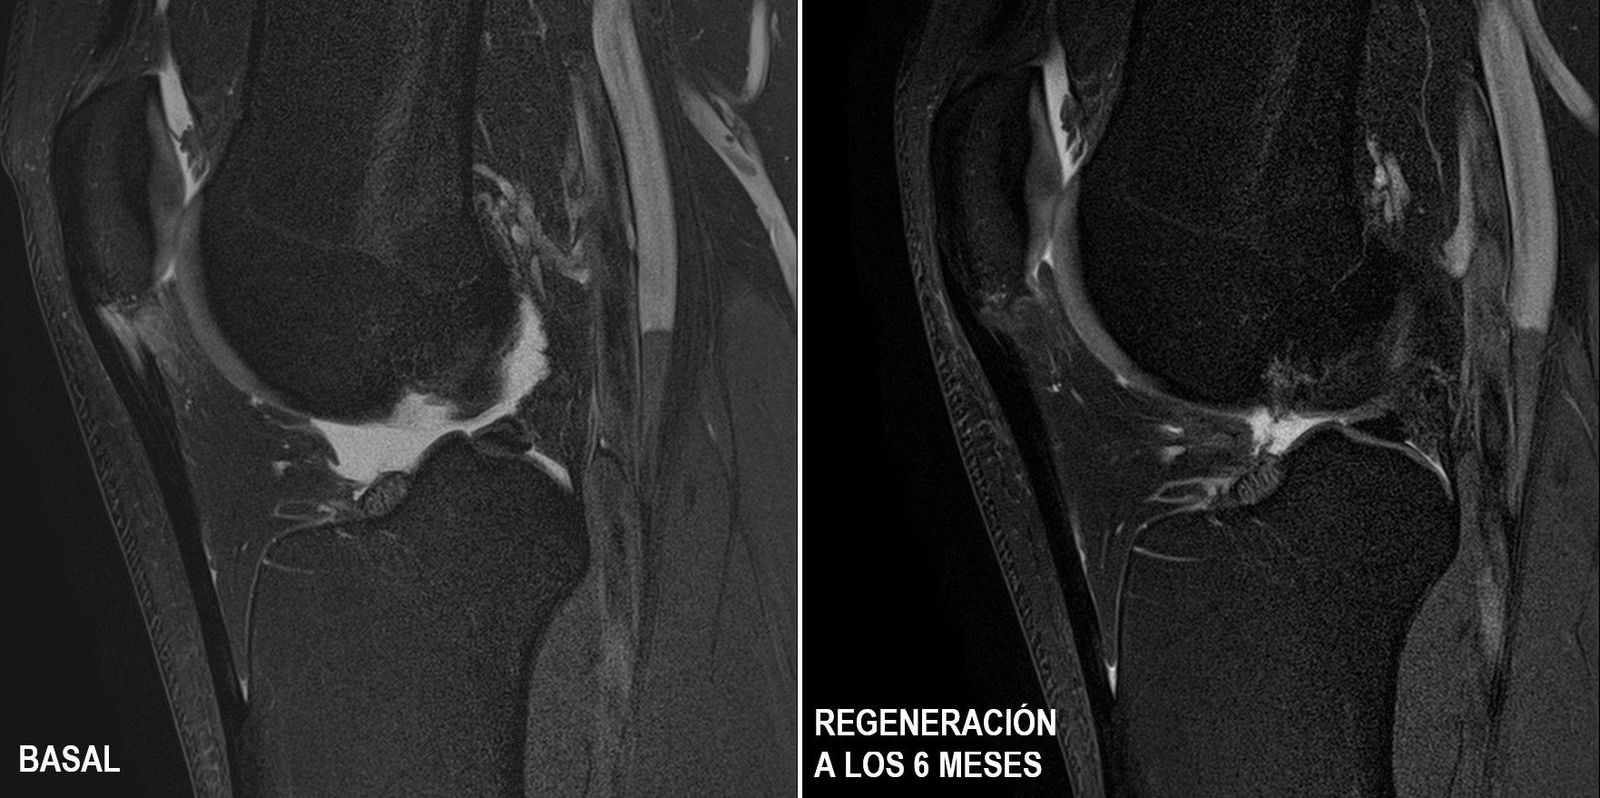

Los resultados a los seis meses del ensayo, que ha sido realizado por los doctores Robert Soler, Lluís Orozco y Gil Rodas muestran un grado de regeneración sin precedentes en el cien por cien de los pacientes, con disminución del dolor y una reincorporación a la práctica deportiva a los dos meses. Estos resultados acaban de ser publicados por la revista 'American Journal Sports Medicine' (AJSM) en su número de mayo.

A los 6 meses, el grupo tratado con células madre mesenquimales cultivadas mostró por primera vez la restauración de la estructura del tendón hasta recuperar un 40 por ciento de la lesión en todos los pacientes, mientras que el grupo tratado con PRP no mostró ni evolución ni regeneración, incluso superado el periodo de 6 meses.